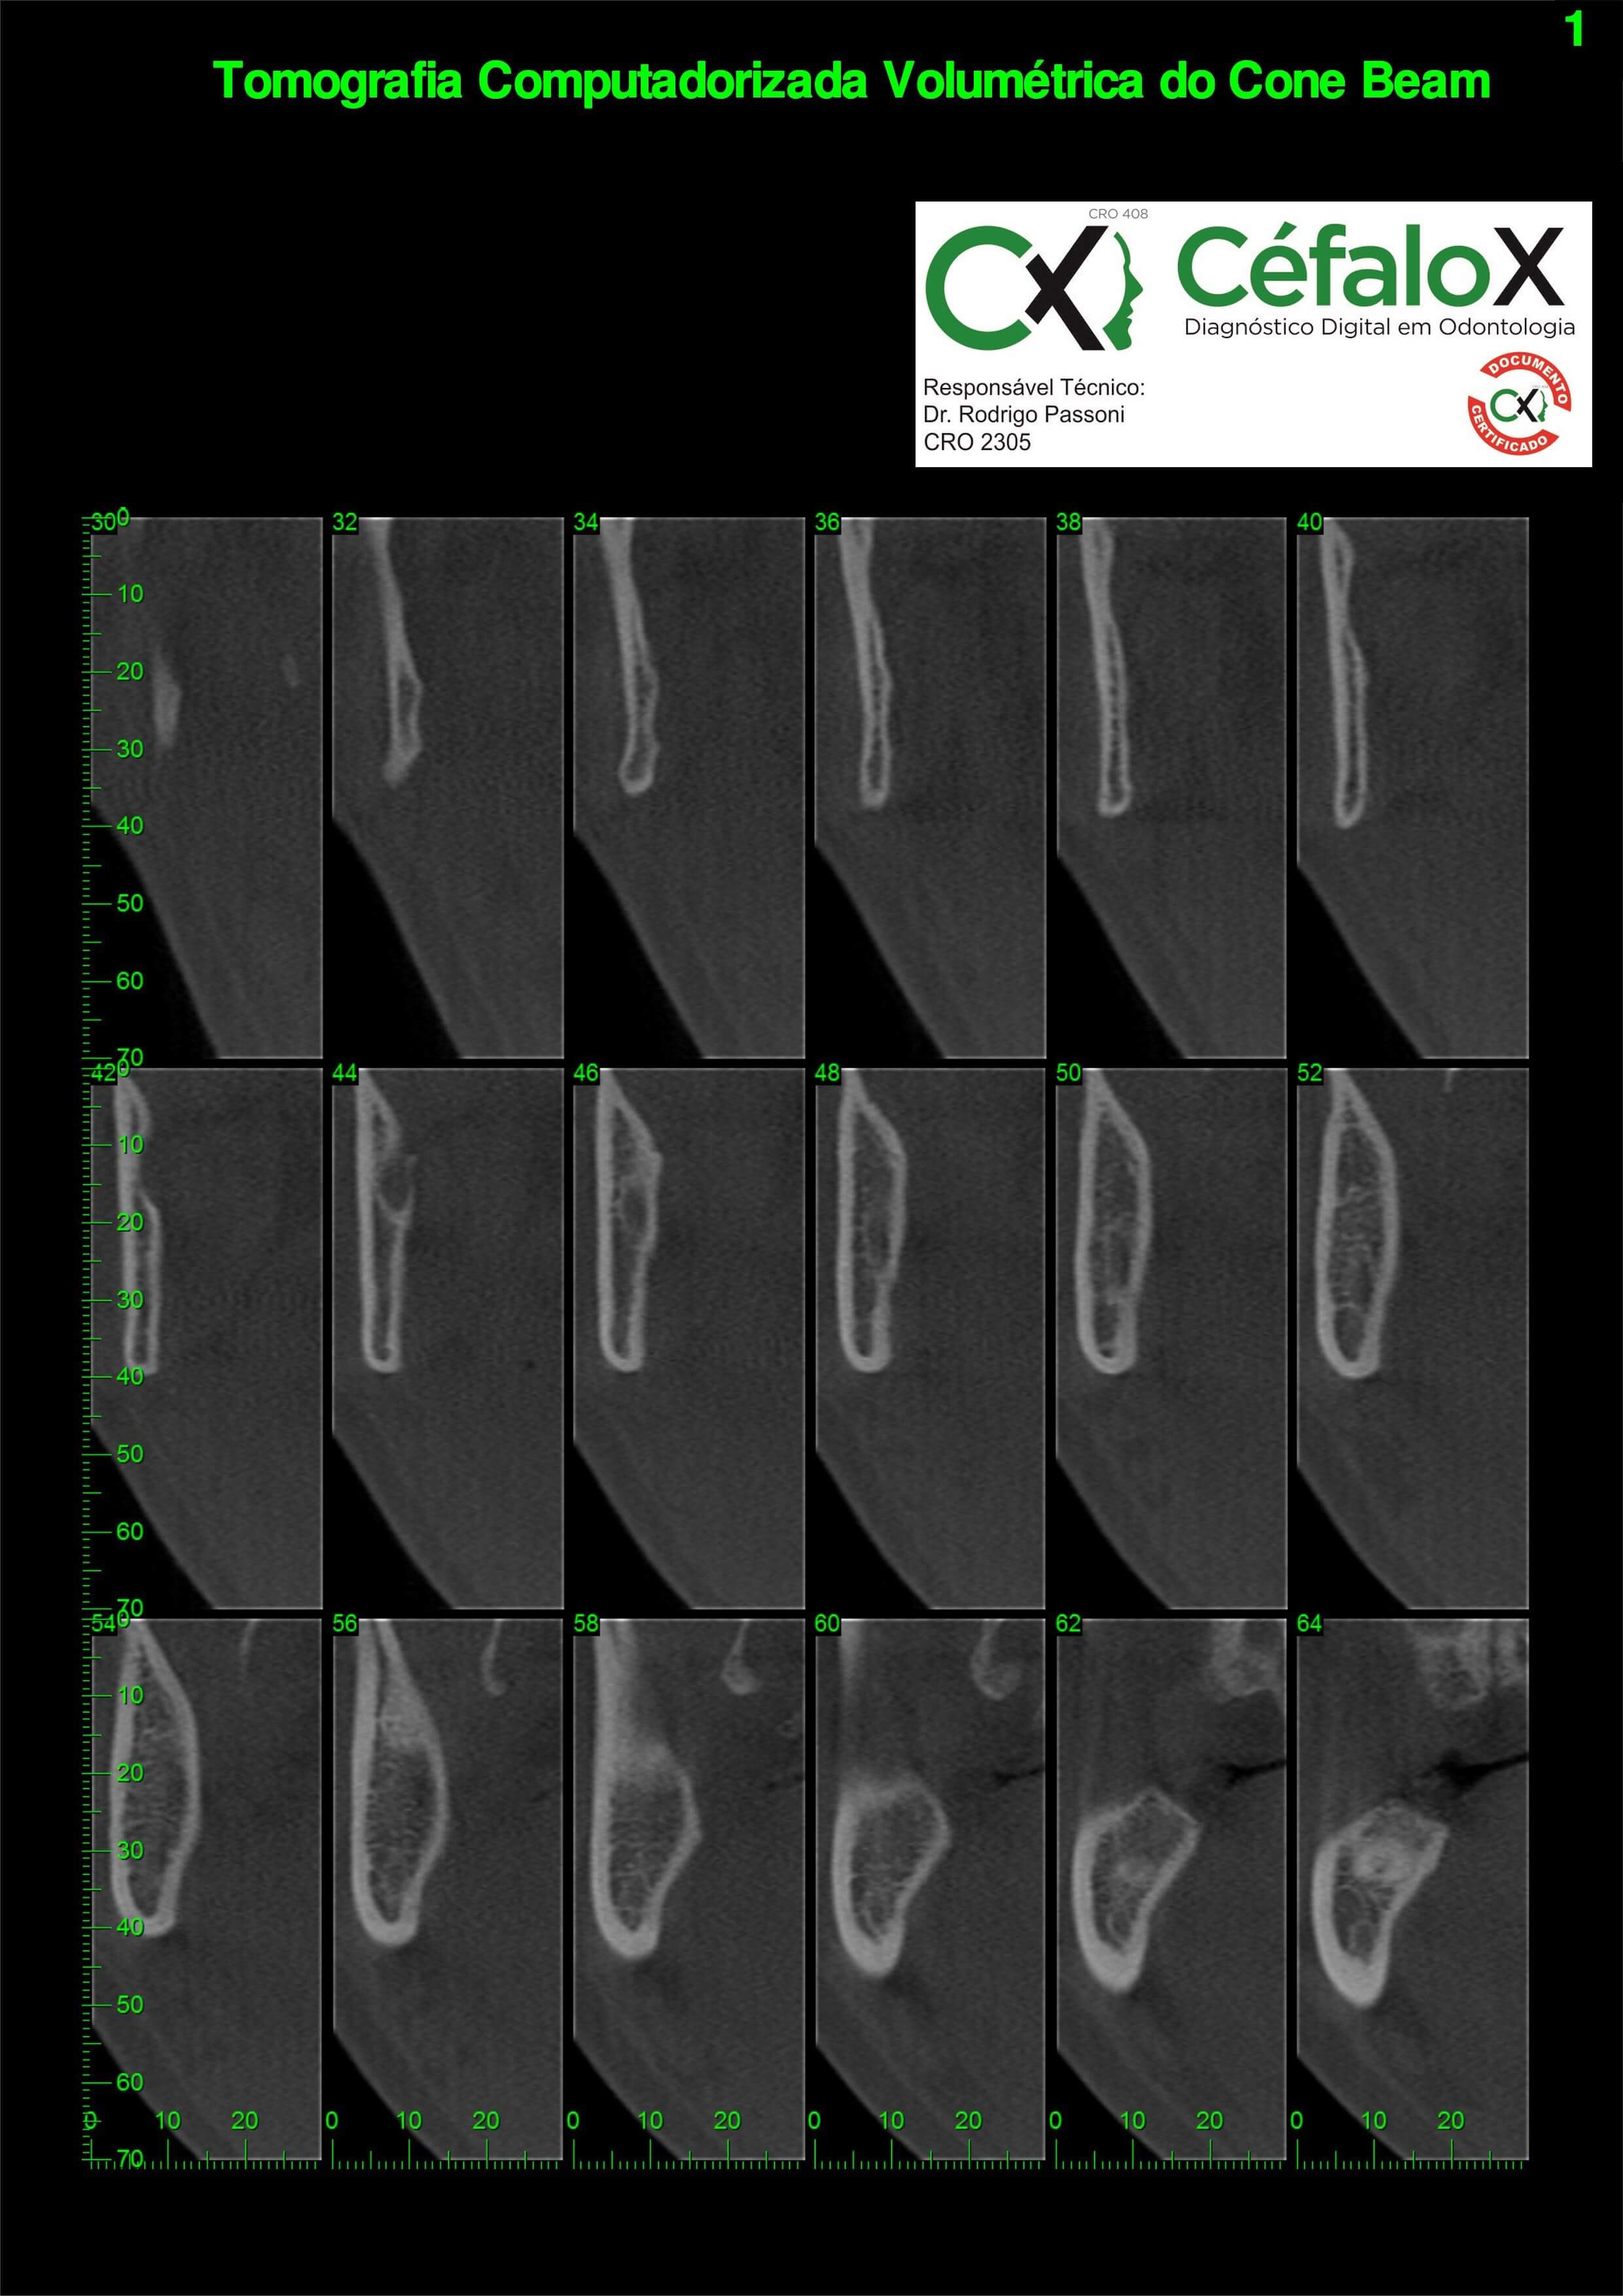

TC de face (do Hióide à Glabela), reconstrução 3D do tecido ósseo, radiografia panorâmica, telerradiografia lateral com traçado, cortes transversais e axial de maxila e mandíbula e arquivo DICOM- entregue em pasta de Pvc.

TC de face (do Hióide à Glabela), reconstrução 3D do tecido ósseo, radiografia panorâmica, telerradiografia lateral e frontal com traçado, cortes transversais e axial de maxila/mandíbula e arquivo DICOM – entregue em pasta de Pvc.

TC de face (do Hióide à Glabela), reconstruções 3D do tecido mole/ósseo/vias aéreas, radiografia panorâmica, telerradiografia lateral e frontal com traçado, cortes transversais e axial de maxila/mandíbula, ATM e arquivo DICOM – entregue em pasta e caixa de Pvc.